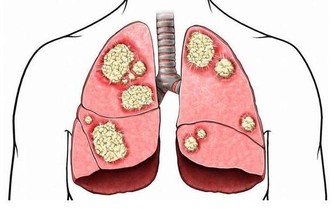

腎貯藏精氣,為人體生殖、造血、生長發育、防衛病邪的基礎物質,平衡身體水液代謝,與膀胱合作排泄尿液,負責納氣,協調呼吸運動,主骨生髓,養腦益智,促進頭髮生長,腎氣通耳,控制聽力,控制二陰的開合。